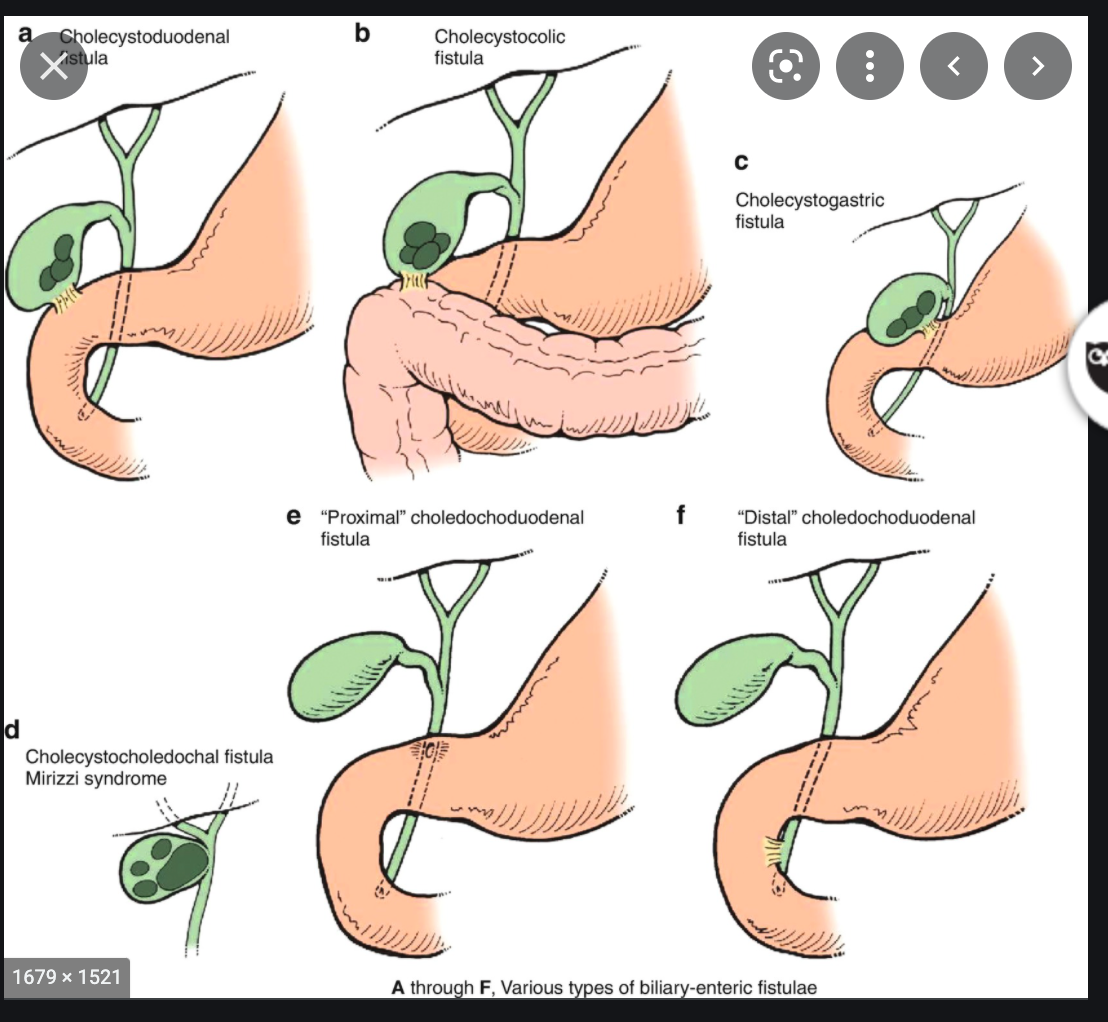

Types of biliary enteric fistulae

- Biliary gastric

- biliary duodenal - most common, may cause gallstone ileus

- biliary-colonic

- Bouveret syndrome: obstruction of stomach or duodenum by stone

- Iatrogenic

- ERCP, Surgical

- most common cause for biliary ductal gas